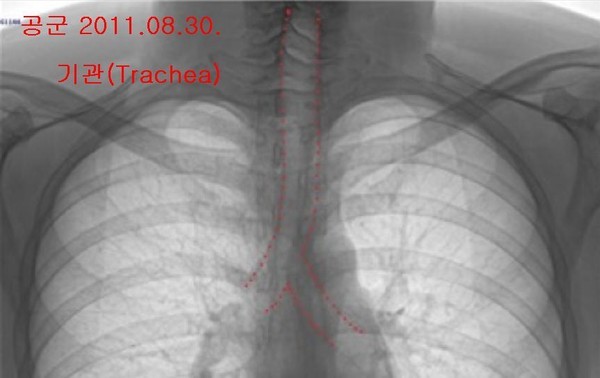

- ▲ 양승오 박사 재판 피고인들이, 유력한 증거로 꼽고 있는 박주신씨 명의의 엑스레이 3장. 왼쪽부터 공군훈련소(2011년 8월 촬영)-자생병원(2011년 12월 촬영)-비자발급용 엑스레이(2014년 7월 촬영). ⓒ 뉴데일리DB

박주신씨의 신체를 촬영한 것으로 알려진 엑스레이는 모두 3장이 있다. 이 중, ‘공군훈련소 입소 당시 엑스레이’(촬영일자 2011년 8월 30일, 이하 공군 엑스레이)와, 주신씨가 ‘비자발급을 위해 촬영한 세브란스병원 엑스레이’(촬영일자 2014년 7월 31일, 이하 비자발급용 엑스레이)는 피고인들도 박주신씨 본인의 것으로 보고 있다.

반면 피고인들은, 박주신씨가 병역처분 변경을 위해 병무청에 제출한 자생병원 엑스레이(촬영일자 2011년 12월 9일)는, 주신씨가 아닌 대리신검자의 것으로 의심하고 있다.

양승오 박사는 “공군에서 찍은 엑스레이와 비자발급을 위해 찍은 엑스레이에서는 피사체의 제1흉추와 제7경추 극상돌기가 오른쪽으로 휘어있지만, 자생병원에서 찍은 영상에서는 정방향으로 나온다”며, “이 2개만 가지고도 동일인으로 볼 수 없다”는 소견을 밝혔다.

이어 양 박사는 박주신씨 명의 엑스레이 3장에서 공군-비자발급용 엑스레이와 달리 자생병원 엑스레이에서만, 기관(氣管)의 모양이 다른 점, 흉곽의 좌우 길이가 더 긴 점 등을 근거로 들며, 피사체를 동일인으로 볼 수 없다는 의견을 나타냈다.

- ▲ 박주신씨 명의 엑스레이 3장에서 나타나는 기관(氣管)의 주행 형태. 자생병원 엑스레이는 직선으로 뻗어 있으나, 공군-비자발급용 엑스레이는 왼쪽으로 휘어있다. ⓒ 의료혁신투쟁위 제공